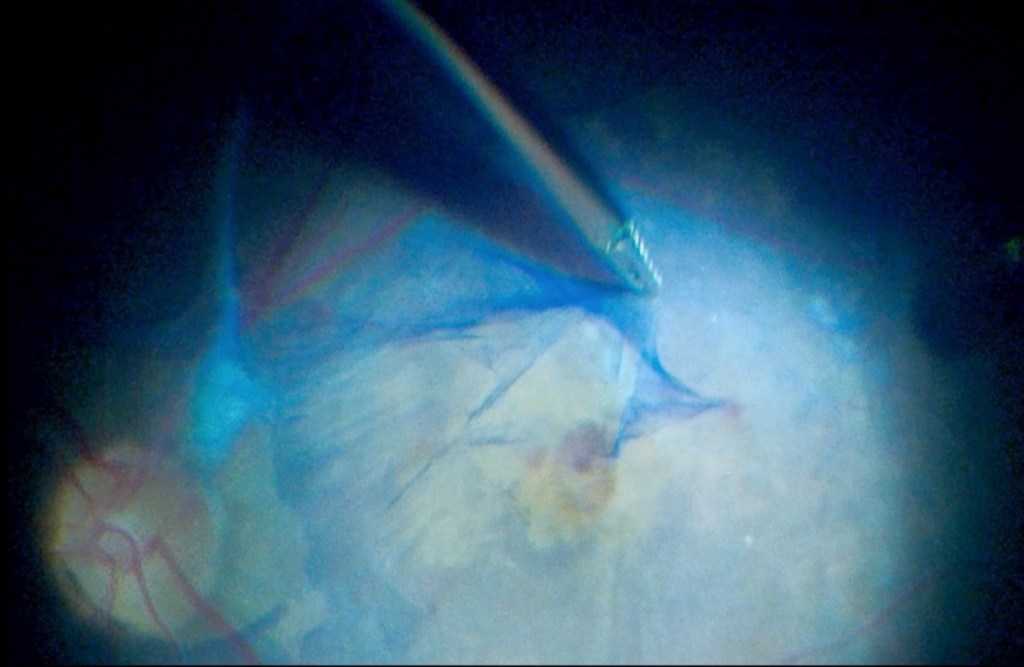

La procédure a débuté par l’extraction de la cataracte, suivie d’une vitrectomie standard par pars plana, réalisée à travers trois orifices avec un calibre de 23. Une prolifération fibrovasculaire dense a été observée au niveau de la zone maculaire. Une pince crantée de calibre 25 a été utilisée pour engager et soulever le tissu fibreux, qui a été pelé en bloc. Deux échanges air-fluide ont été effectués au cours de l’intervention.